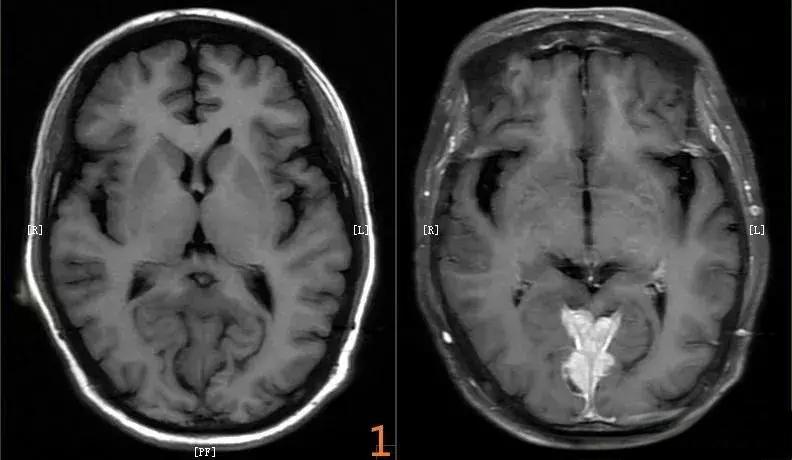

磁共振成像(MRI)是一种利用磁场和射频波生成人体内部结构详细图像的检查方法。近年来,随着医学影像技术的快速发展,MRI增强扫描在临床诊断中的应用越来越广泛。

MRI增强扫描的核心原理是通过静脉注射造影剂,提高病变与其周围组织的对比度。目前临床使用较多的造影剂为钆螯合剂。这种造影剂能够影响组织的纵向弛豫和横向弛豫,从而在MRI图像上形成良好的对比度。与传统的MRI平扫相比,增强扫描能够更清晰地显示病变与组织间的对比,明确病变的大小、范围、性质、血供和与周围组织器官的关系。

MRI增强扫描在临床应用中具有独特的优势。首先,它能够发现并明确许多在平扫中难以显示的病灶。例如,对于一些体积较小或与正常组织没有明显差别的病变,增强扫描可以通过观察病变的血液供应情况来区分。其次,MRI增强扫描在血管性病变、头颅及全身血管造影中也发挥着重要作用。通过观察造影剂在血管中的分布,可以更清晰地显示正常血管及病变血管。